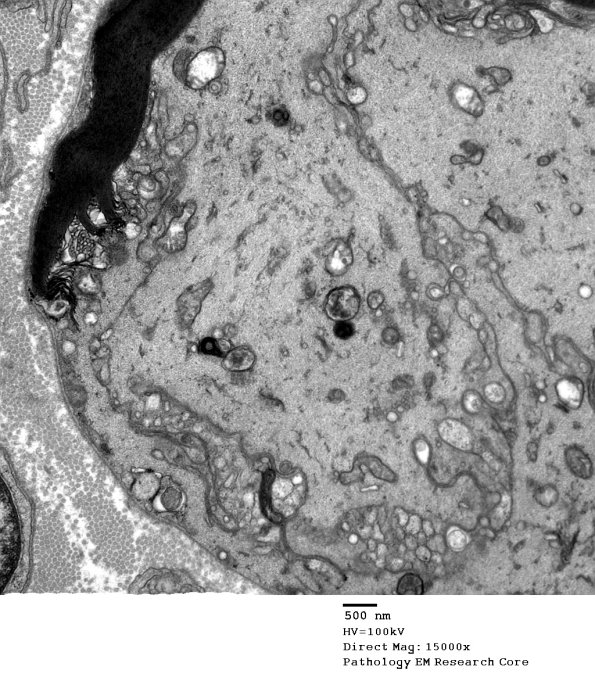

Higher magnification of image #16C1. (electron micrograph)